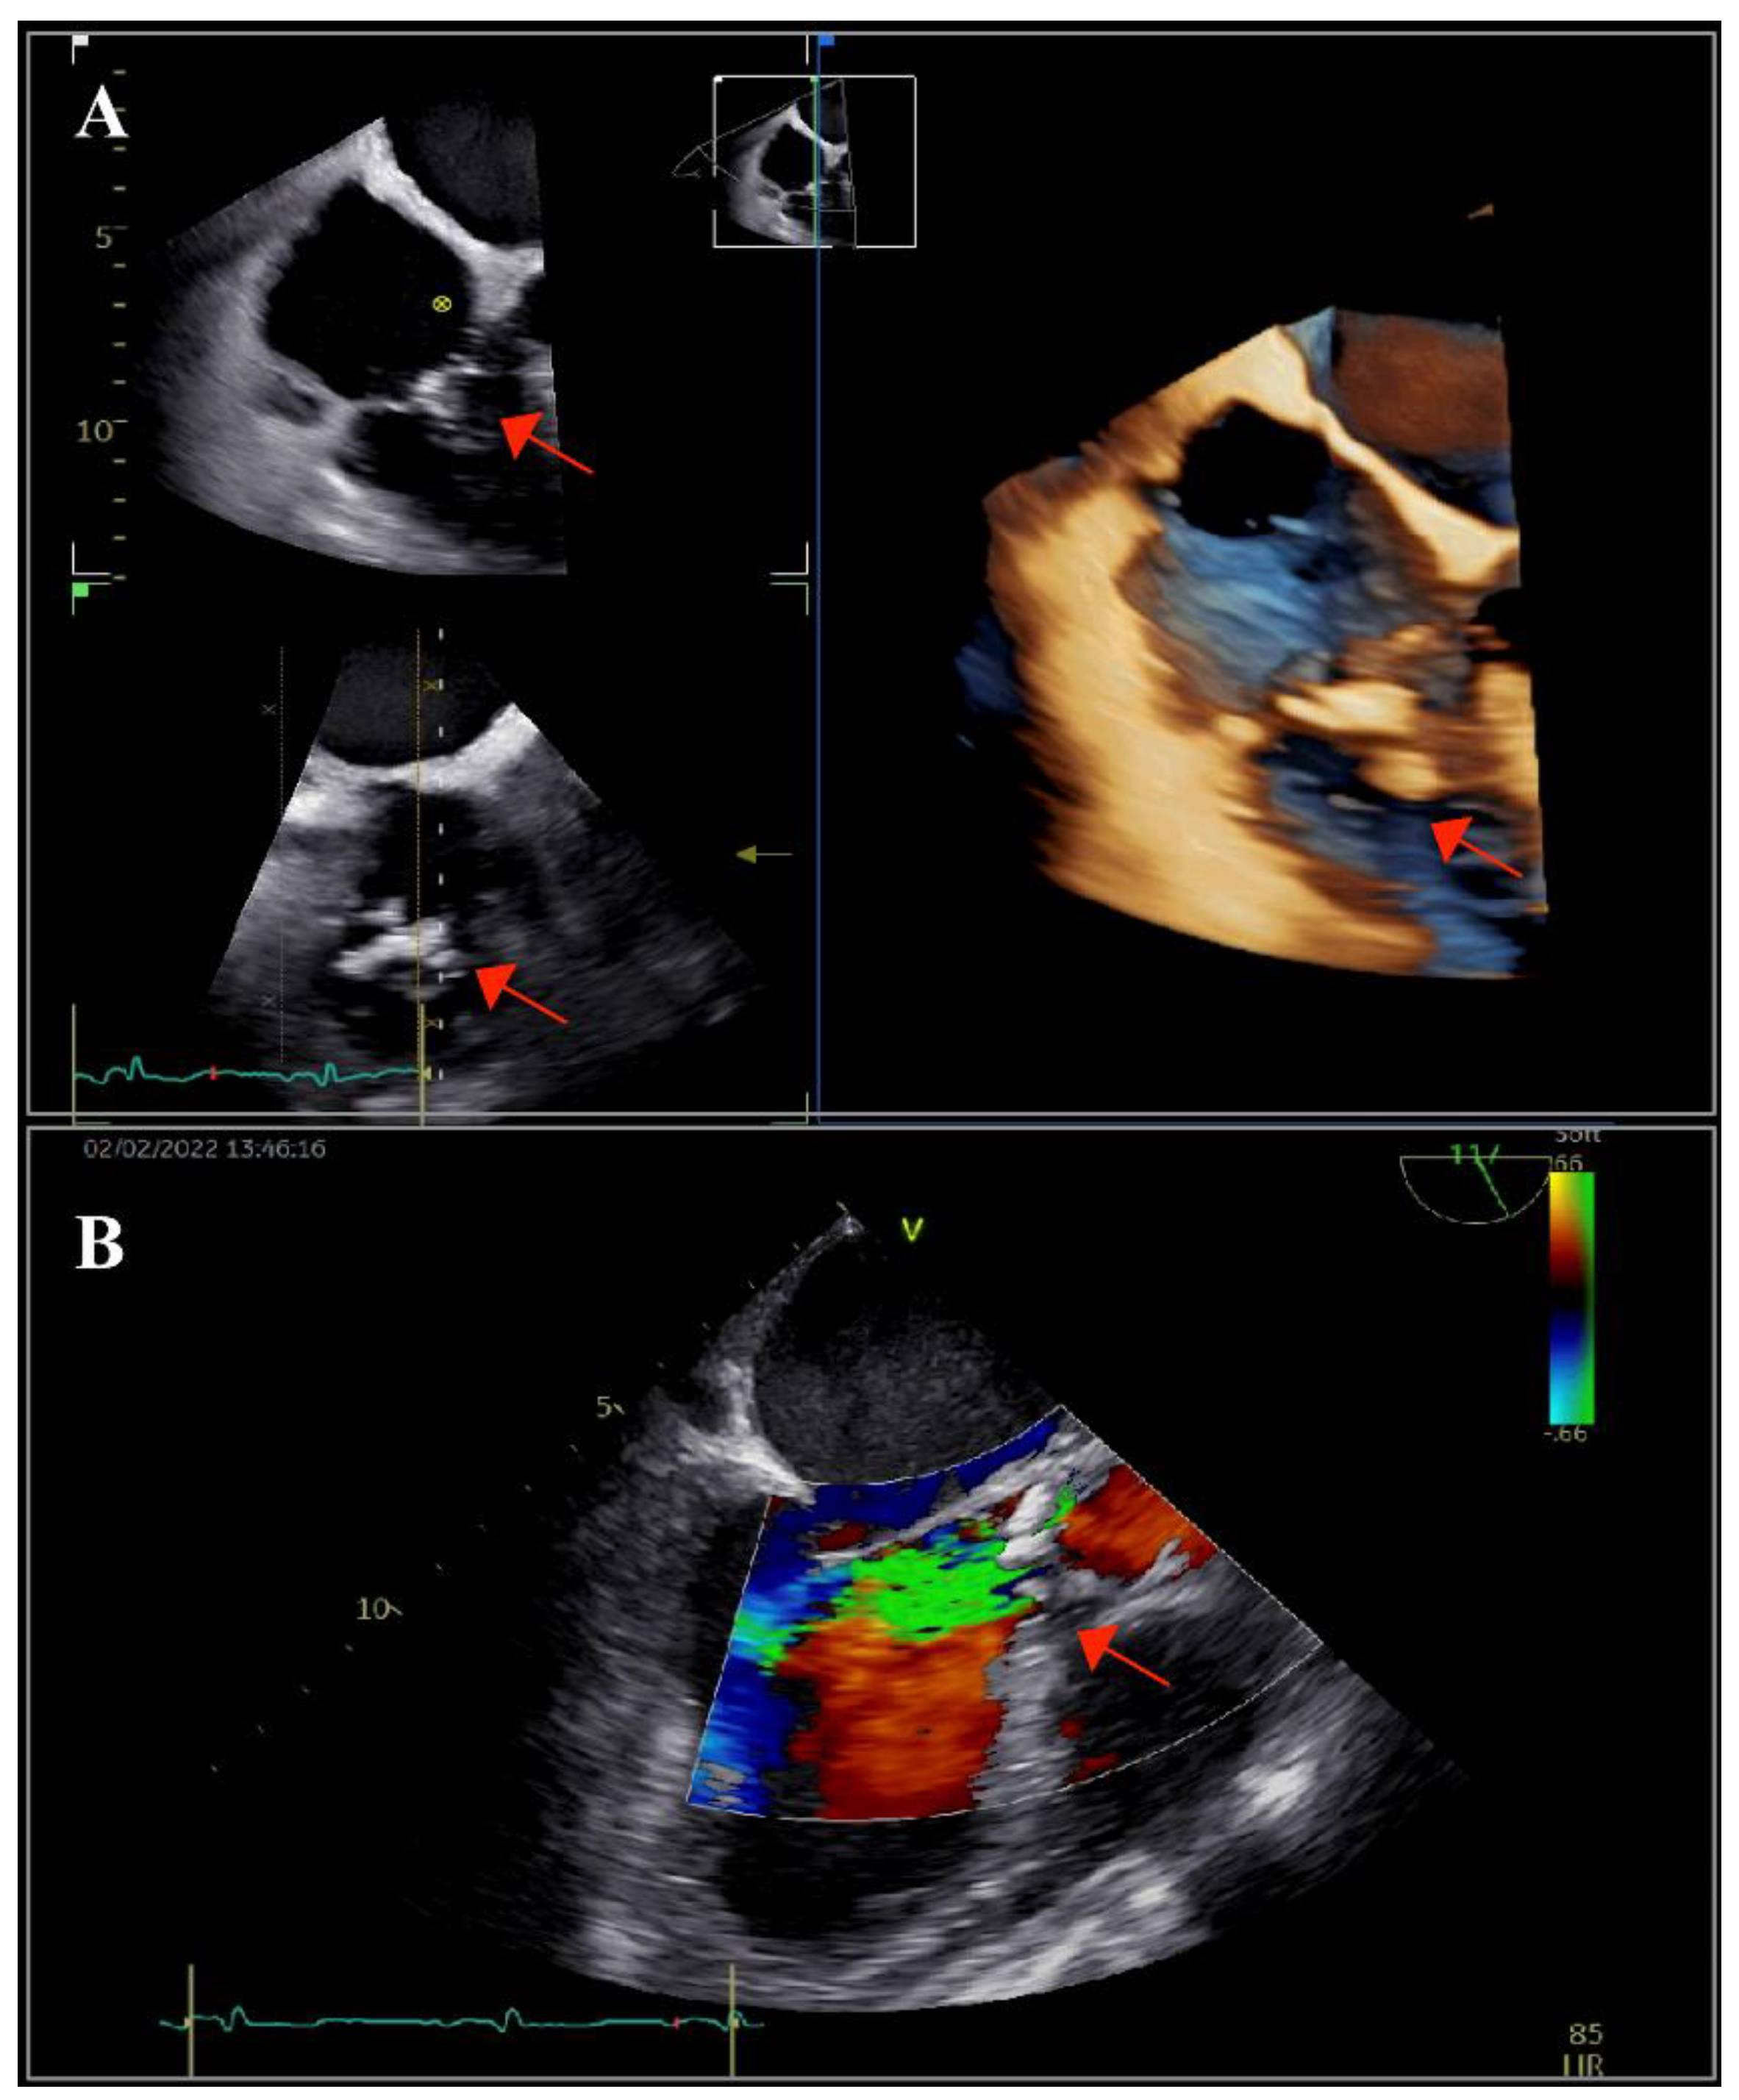

The patient underwent transthoracic echocardiography, which revealed severe aortic and tricuspid regurgitation, moderately reduced left ventricular ejection fraction (35%) and preserved right ventricular systolic function. There were multiple small mobile masses attached to the aortic valve, indicating vegetations. Because the tricuspid valve was thickened, tricuspid endocarditis was also suspected. These findings were corroborated by transesophageal echocardiography (TOE), which revealed multiple vegetations at the level of both the aortic and tricuspid valves that were better visualized with three-dimensional acquisitions (Figure 1). There were no paravalvular complications. Furthermore, TOE visualized an inhomogeneous mass at the level of the superior vena cava (SVC), prolapsing into the right atrium, indicating the possibility of a fibrin sheath subsequent to the removal of the CVC or thrombus (Figure 2).

Figure 2. Multi-dimensional transesophageal echocardiography acquisitions showing an inhomogeneous calcified mass at the level of the superior vena cava, with right atrial protrusion (arrow).